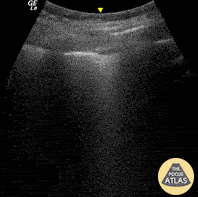

What is seen in this ultrasound?

Normal lung sliding and A-lines.

A-lines are defined as horizontal, hyperechoic reverberation artifacts that appear at regular intervals below the pleural line, representing normal air-filled lung parenchyma. The presence of both lung sliding and A lines is considered the normal sonographic pattern of a well-aerated lung